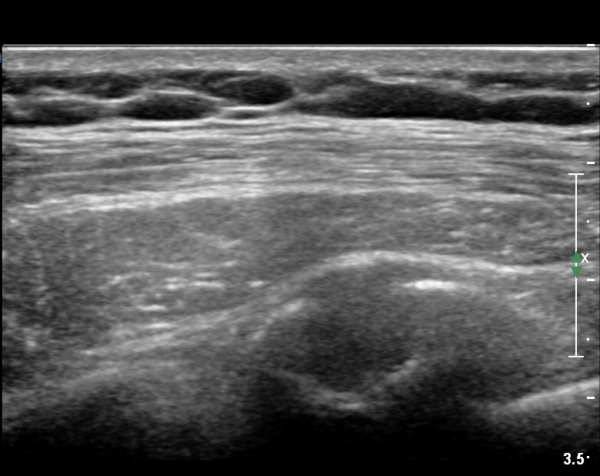

lin longitudinal scan of 7th. rib, appearance of bony mass(protrusion) just like callus(image 1).

on moving of prove a little, there is bony protrusion(osteoblastic lesion) and hypoechoic(osteolytic)  lesion(image 2, 3, 4).

in transverse scan, visualization of osteoblastic mass with central osteolytic lesion(image 5, 6).

As like this case, visualization of osteoblastic lesion and osteolytic lesion in simultaneously  suggests a malignant mass.